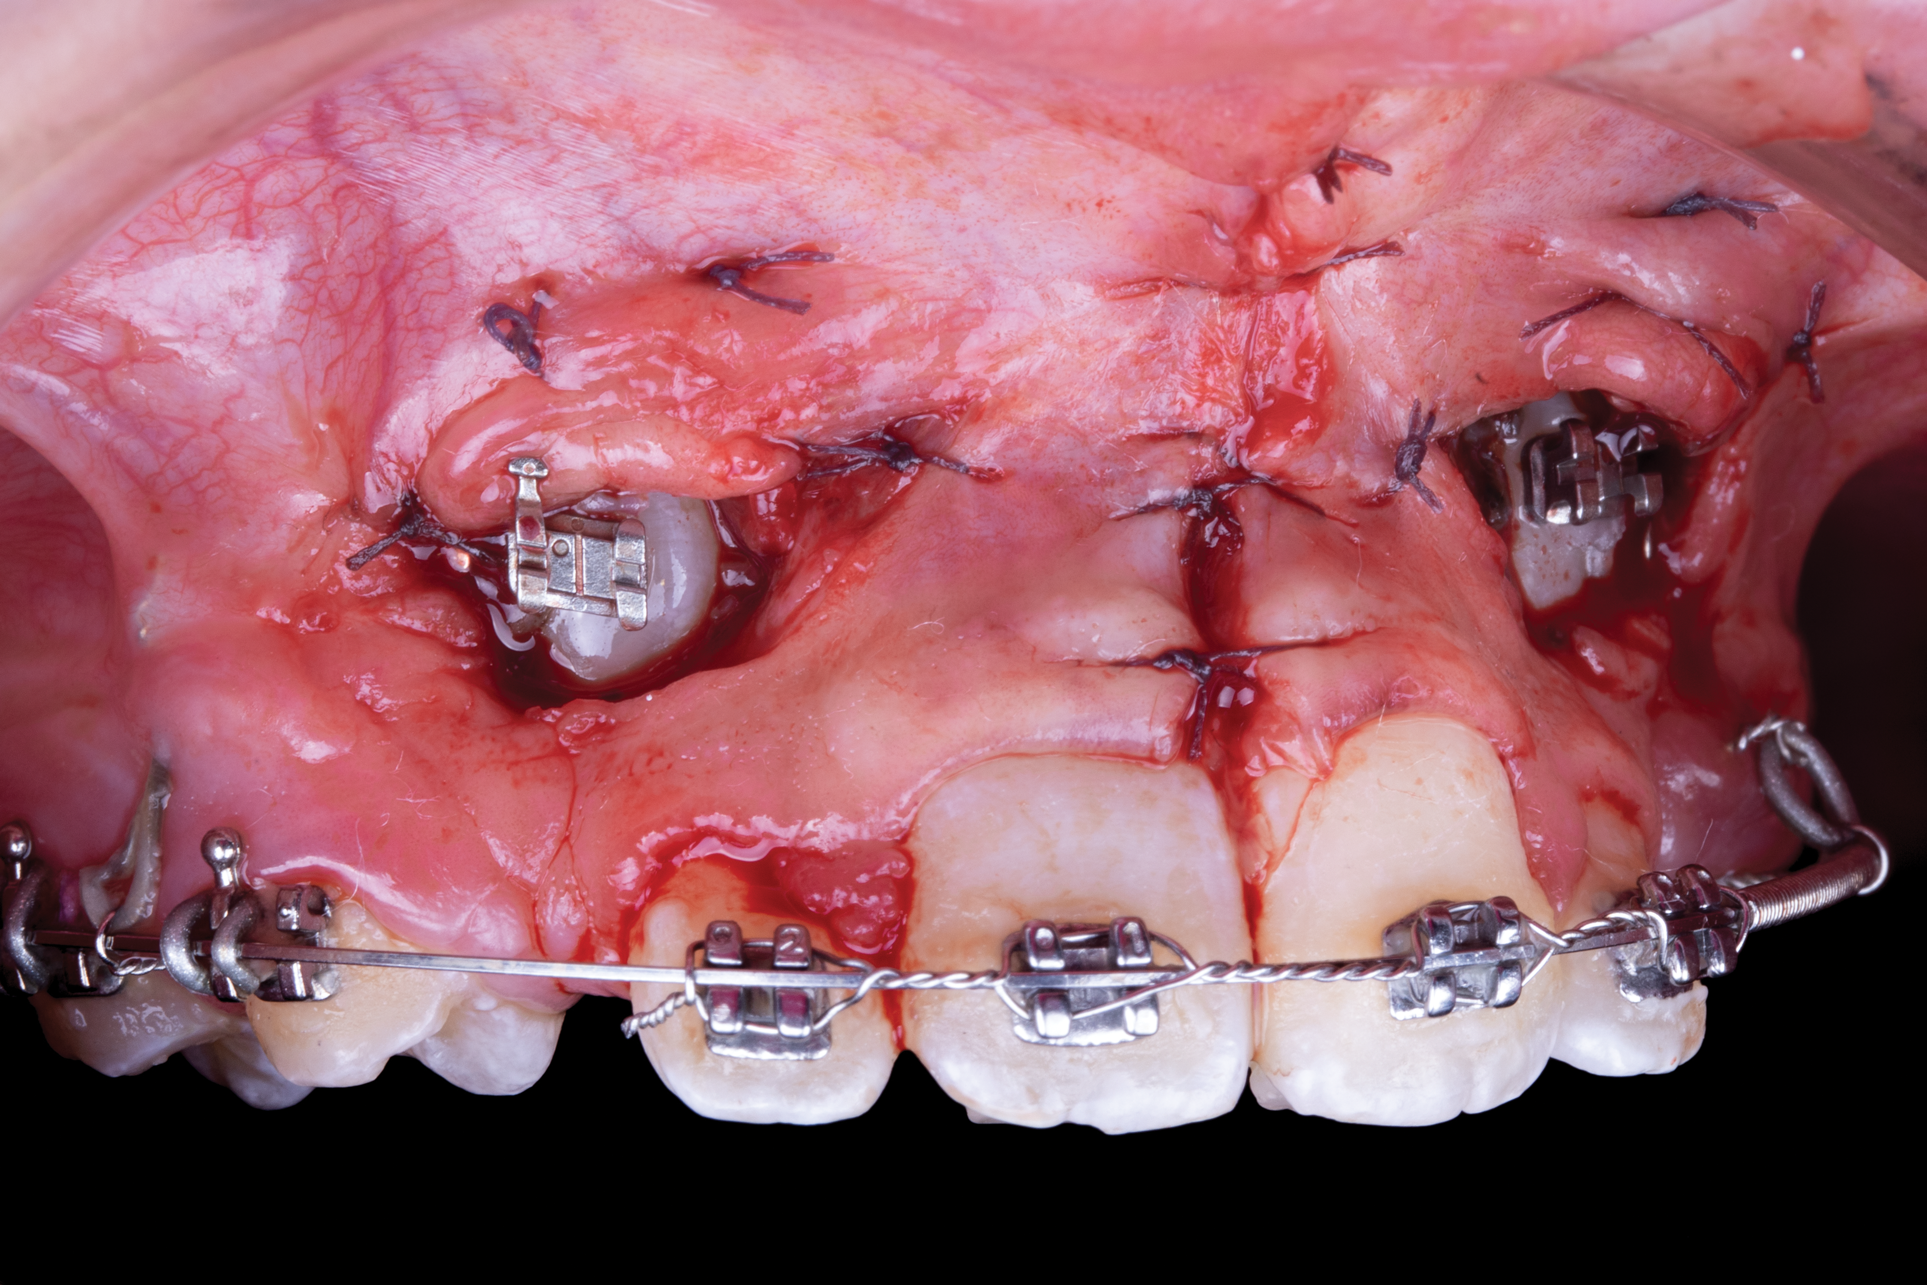

Fig 6. Use of apically positioned flap to manage bilateral facially impacted canines. During the same procedure a midline frenectomy was performed after the exposure and bilateral brackets were placed (Fig 6). Orthodontic traction was performed, which allowed both canines to be properly placed in the upper arch (Fig 7).

Figure 6

Fig 7. Use of apically positioned flap to manage bilateral facially impacted canines. During the same procedure a midline frenectomy was performed after the exposure and bilateral brackets were placed (Fig 6). Orthodontic traction was performed, which allowed both canines to be properly placed in the upper arch (Fig 7).

Figure 7